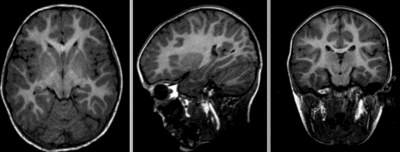

this is the fixed reference image. All images are aligned into this space lleft this is the moving image. The transform is calculated by matching this to the reference image

fixed image/target moving image